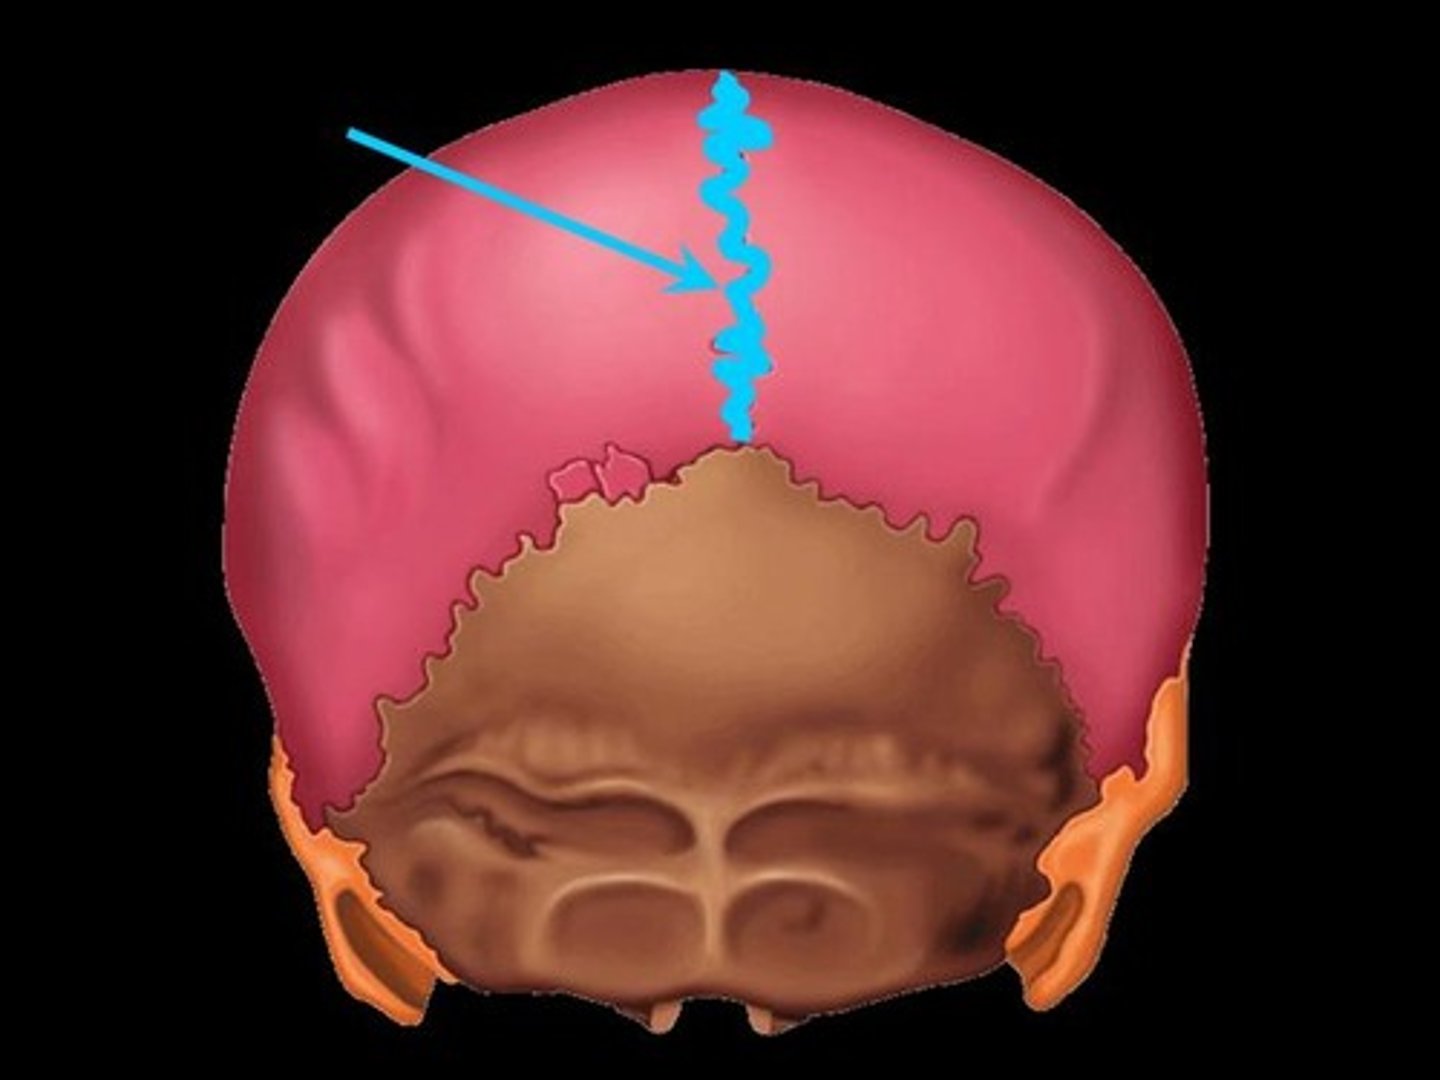

4 Main Sutures of the Skull

- Saggital

Saggital Suture

Suture that separates the left and right parietal bone